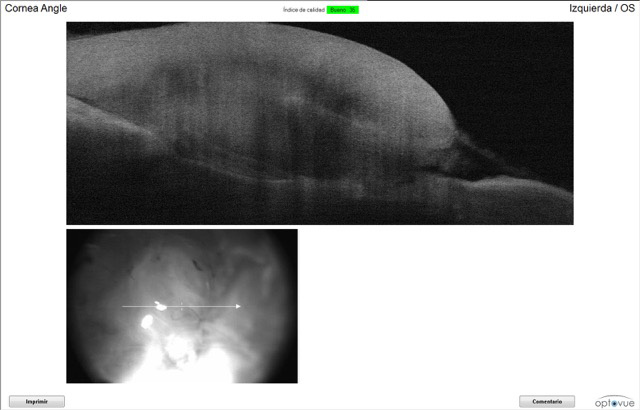

- OCT

El test de fluoresceína solo dio positivo en las zonas de los puntos. La OCT nos mostró cómo el injerto y el coágulo cada vez están mas adheridos a la córnea de Iker. La tonometría se le realizó para controlar la hipertensión ocular, y los valores fueron normales. El test Dazzle dió positivo (responde a las luces), tiene reflejos pupilares.